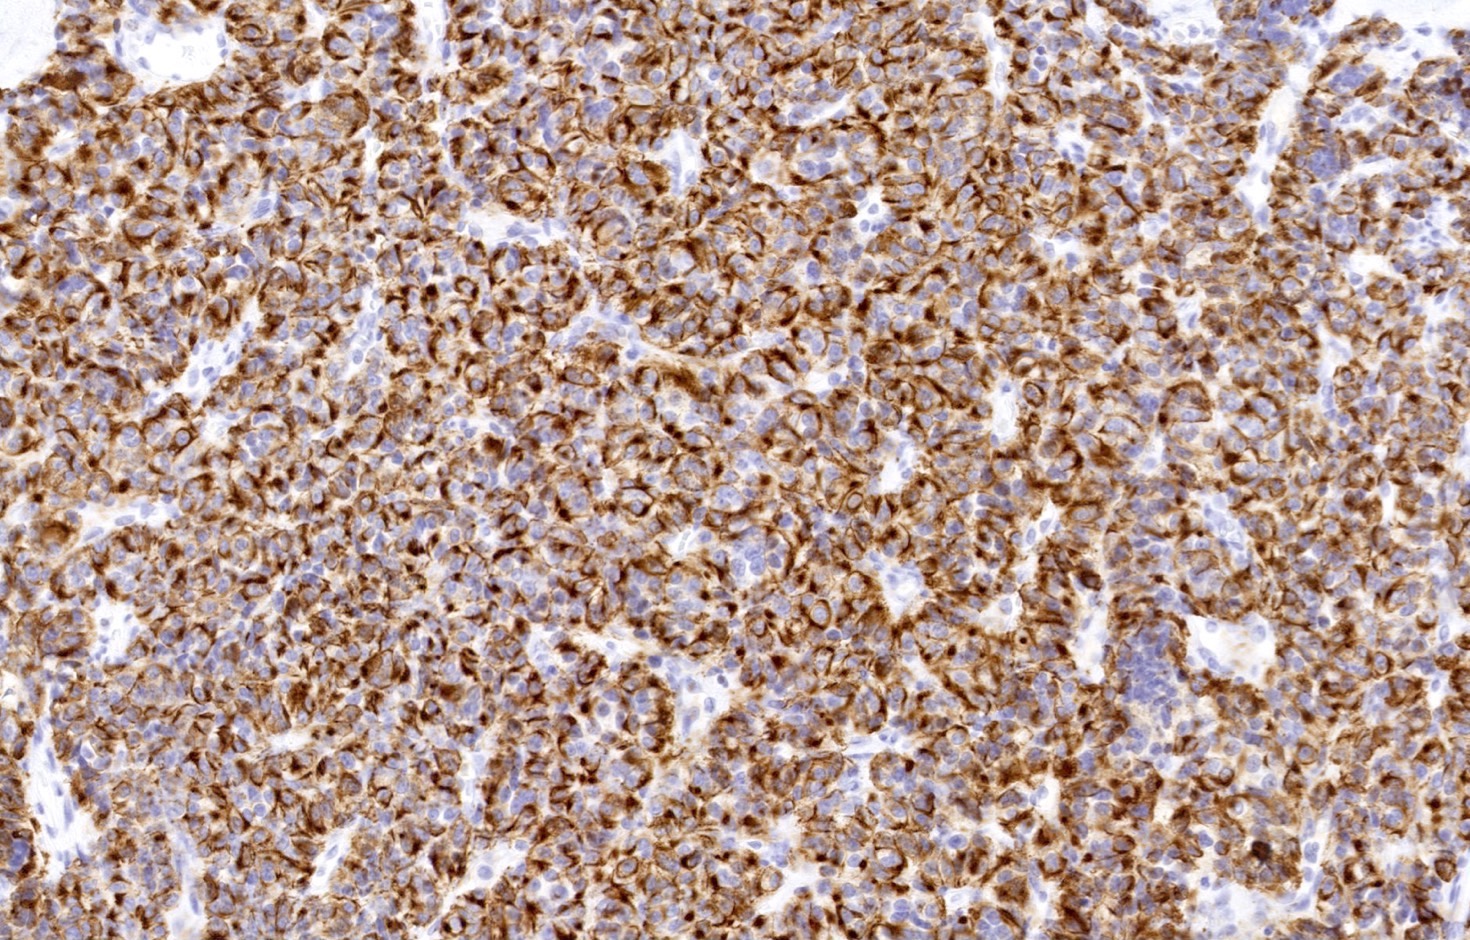

Positive stains

- Chromogranin, synaptophysin, CD56 and INSM1: diffusely and strongly positive (Mod Pathol 2019;32:100)

- Pancytokeratins: positive, useful to distinguish from paraganglioma (Arch Pathol Lab Med 2010;134:1628)

- Ki67 (expected < 20%)

- Ki67 proliferative index does not have an impact on tumor classification; WHO classification states that is desirable to routinely report its value

- Mostly useful to discriminate between high grade neuroendocrine tumors (small cell carcinoma and large cell neuroendocrine carcinoma), on small or crushed biopsies in particular (Arch Pathol Lab Med 2018;142:947)

- Utility of differentiation between typical and atypical carcinoid is not proven (Virchows Arch 2017;470:153)

- TTF1: useful marker of pulmonary lineage in typical and atypical carcinoids but only positive in < 50% of cases

- TTF1+ carcinoids are more commonly seen in peripheral lesions and staining is commonly focal and weak (Hum Pathol 2004;35:825)

- Rb: preserved in the vast majority of pulmonary carcinoids (Transl Lung Cancer Res 2017;6:513)